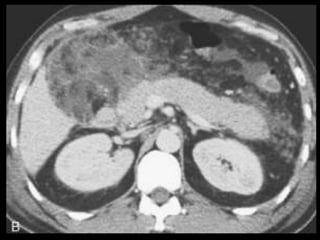

PANCREATITE AGUDA GRAVE

Ocorre em 20-30% dos pacientes com PA;

Caracteriza-se por evolução protraída, insuficiência

de múltiplos órgãos e necrose pancreática;

Necrose pode ser difusa ou esparsa, superficial ou

profunda, e pode afetar qualquer parte do

pâncreas;

A necrose ocorre logo de início, em 24-48 horas,

ela permanece estável, com raras exceções.

Os resultados TC são melhores indicadores

prognósticos que sistemas de escores numéricos,

devido a sua maior sensibilidade e especificidade.

A administração de contraste IV é essencial,

especialmente em pacientes com PA grave, para

visualizar o pâncreas, diferenciar a glândula de

coleções líquidas adjacentes e do tecido

inflamatório peripancreático e demonstrar a

necrose pancreática.

Áreas focais ou difusas de realce diminuídas ou

ausente à TC contrastada dinâmica constituem

áreas de isquemia ou necrose.

TC tem precisão geral de 87% com S e E de 100%

para necrose extensa e 50% com áreas menores.